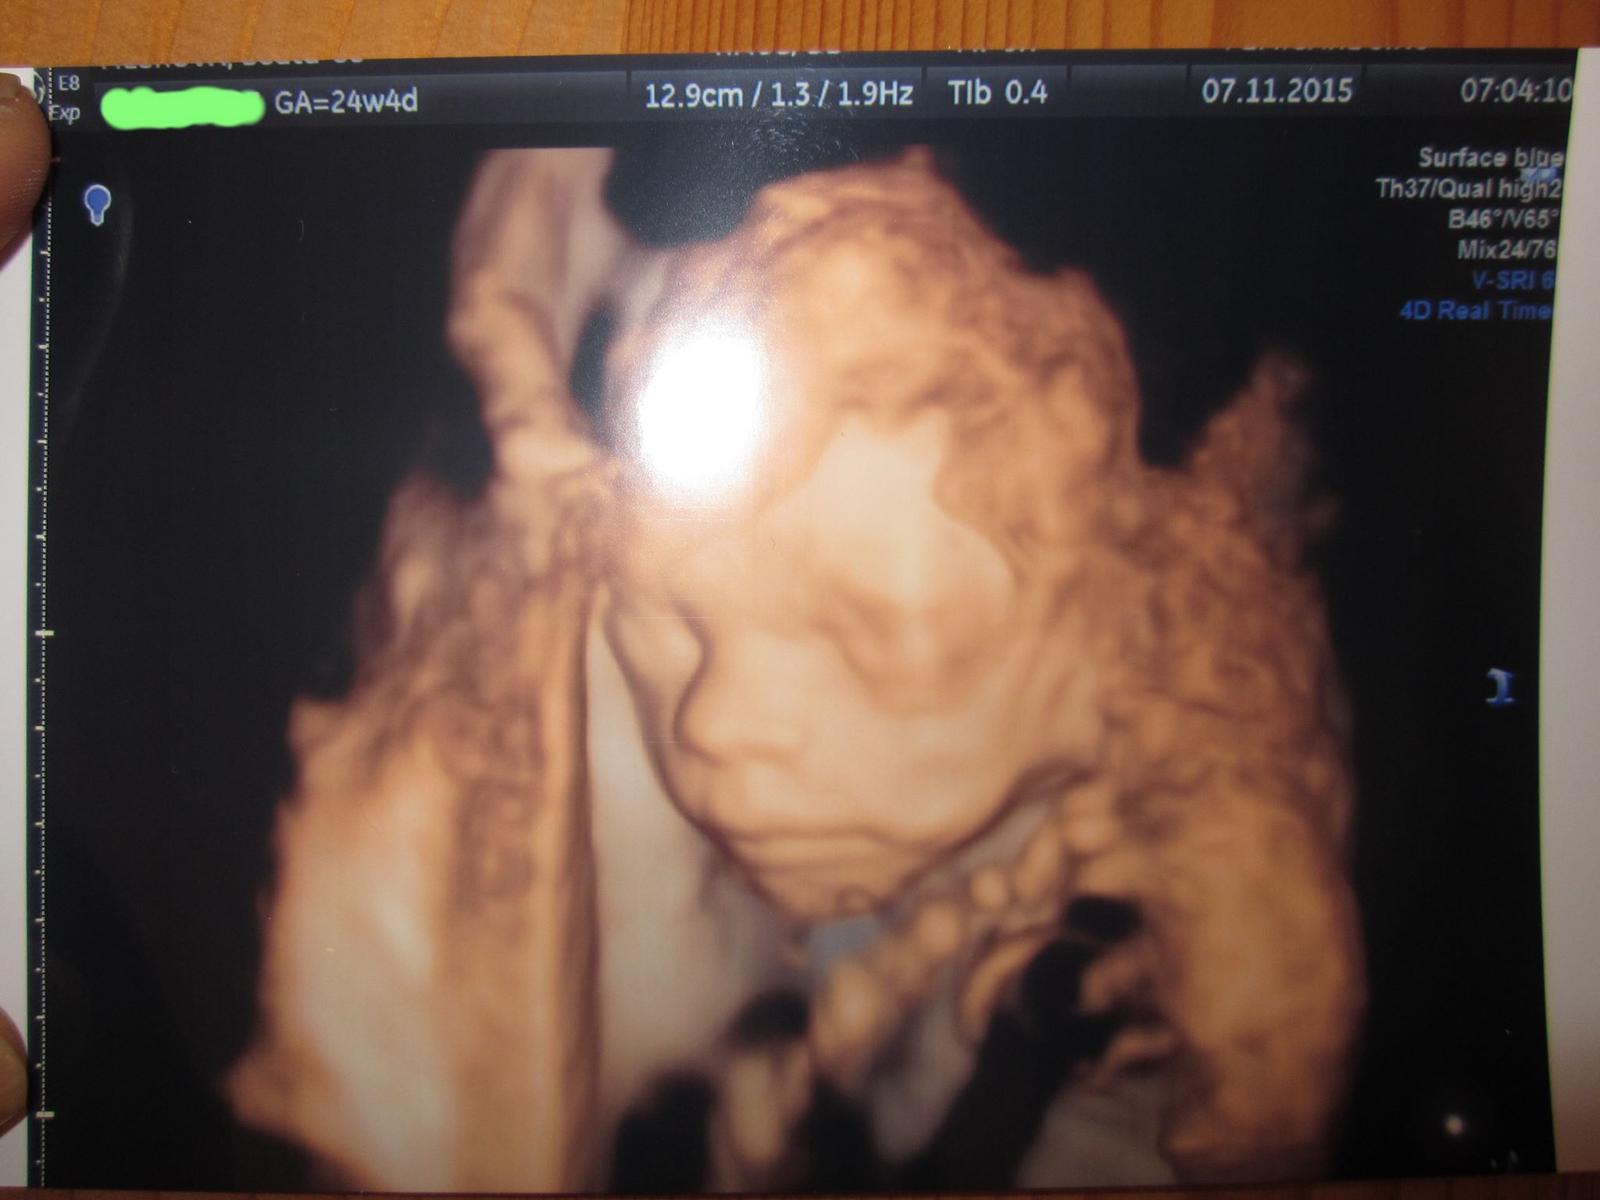

@gabuchah inak tu je nas fesacik 😎 😀

@beaa jehooo, krásny 🙂 po kom bude mať tak krásnu pusinecku? 🙂

@aber Jeeej, tá ručička 🙂 to máš krásne detailné fotky 🙂

@beaa krásna, taká veľká, to bude fešák 🙂 už teraz je, len ešte nech sa modeluje pekne 🙂

@gabuchah nos po mužovi a pery nás oboch, obaja máme veľké 😊😊😊veď aj tvoje malé má krásnu detailnu fotku 😊to som fotila z cd, lebo fotku nám zabudol vytlačiť 😊

@gabuchah táto je asi top, som sa druhý krát zamilovala ,si veľmi zlatá 😊😊😊😊